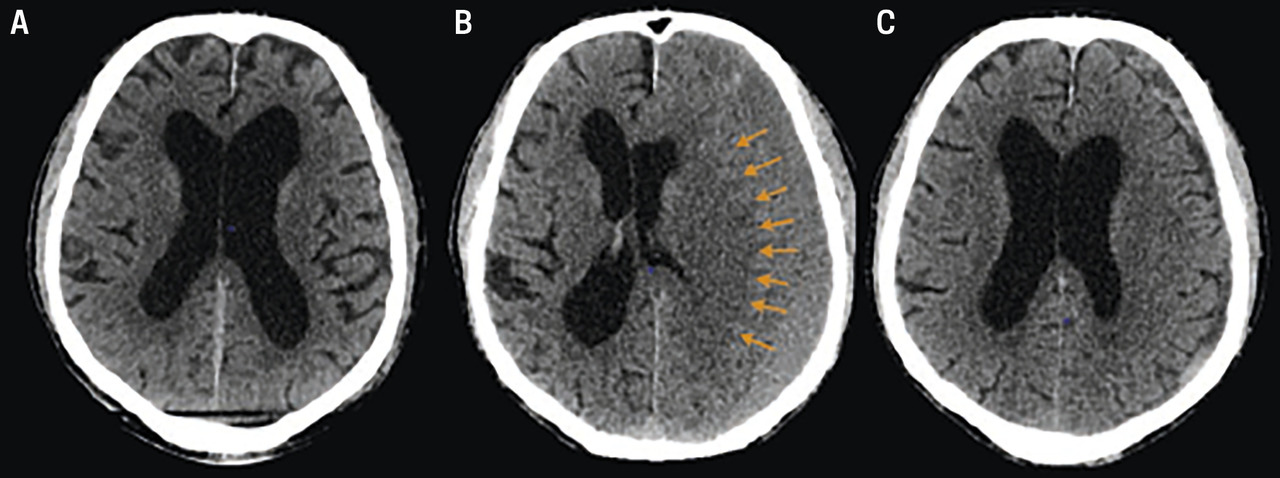

Au scanner cérébral :

– hypo- (hématome chronique datant de plus de 3 semaines) ou isodensité (subaigu, < 3 semaines), classiquement en forme de « croissant » péricérébral, avec souvent un effet de masse sur le cerveau (figure) ;

– parfois saignements d’âges différents, voire cloisonnements.